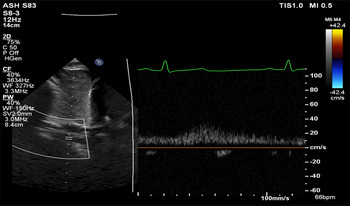

Aortic arch contour was abnormal and appeared to taper at the isthmus. Doppler velocity at the isthmus was within normal limits (1.1 m/s), but a pathologic flow profile with continuation through diastole was noted (Fig 1). Lack of pulsatility and low-velocity continuous flow was found on abdominal descending aorta interrogation (Fig 2). Exam revealed the absence of distal pulses and upper extremity hypertension (139/87 mmHg) with a significant gradient to the lower extremity (72/48 mmHg). CT angiogram confirmed the suspected diagnosis of coarctation of the aorta (Fig 3) and showed extensive vertebral collateralisation supplying the descending aorta. He underwent successful surgical coarctectomy with a lumenal diameter of the excised aortic isthmus found to be less than 1 mm diameter (Fig 4).

Figure 2. Subcostal duplex Doppler showing lack of pulsatility in the abdominal descending aorta. Low-velocity continuous flow is similar to a venous flow profile.

We often grade the severity of obstruction by reporting Doppler-derived pressure gradients, and high-velocity flow through the isthmus is expected in severe coarctation. But, a basic tenet of echocardiography is that flow is required to produce a high gradient. When the coarctation has been longstanding and severe, the presence of collateral flow through the vertebral arteries may diminish flow across the coarctation and the Doppler-derived gradient may be less severe than expected for the degree of obstruction.Reference Houston, Simpson, Pollock, Jamieson, Doig and Coleman3 This case elegantly highlights the significance of Doppler flow profile in making the diagnosis – tracings with continuous antegrade diastolic flow in the arch and low amplitude continuous undulating flow in the abdominal descending aorta are pathologic, and provide important indirect evidence for aortic coarctation.Reference Dijkema, Leiner and Grotenhuis1,2,Reference Shaddy, Snider, Silverman and Lutin4–Reference Doshi and Chikkabyrappa6